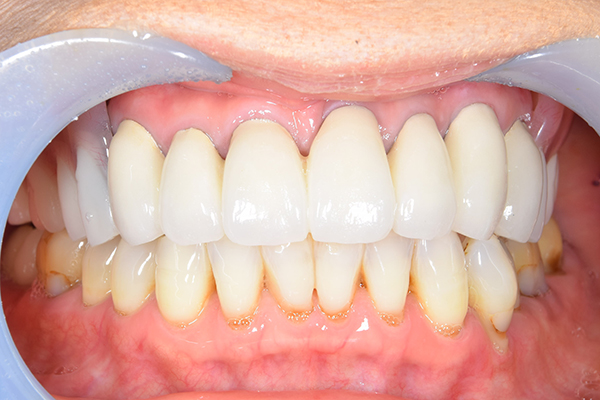

ケース4

(アタッチメントを用いた部分入れ歯)

右上のインプラント周囲炎で、その部分が痛いという患者様でした。 また奥歯で噛むことが難しかったため、前歯を使用することが多くなり、 前歯が前よりも前に出てきていることも気になっていらっしゃいました。

インプラント部以外にも歯周病が進行していましたので、歯周病の治療を行いました。 残念ながらインプラントと、1本の歯が残せなかったため抜歯を行いました。 その後、前歯の出っ張りを修正することと入れ歯の安定を図るため、残っている歯を全てかぶせ物にしていくことになりました。 写真中央は抜歯後に入れた治療用の入れ歯になります。 抜歯後歯ぐきが安定しましたら、入れ歯とかぶせ物の型取りを行いました。

噛み合わせチェックでしっかり奥歯で噛めるようにし、 歯を並べます。 その後、それに合わせて前歯を作っていきます。

最終的な入れ歯用の型取りをします。 シリコンで精密に型取りができました。

こちらが完成したかぶせ物と入れ歯です。かぶせ物にはアタッチメントをつけて金属のバネが見えない構造になっています。 入れ歯自体も金属を使用して、極力違和感がでないように、薄く作成しました。

お口の中に入れた状態です。 非常に見た目もよい出来となりました。 バネがみえないと見栄えが全然ちがいます。

年齢 70代・女性

主訴 奥歯のインプラントが痛い。

前歯がでてきた。

治療期間 6ヶ月

治療費 .メタルボンドクラウン7本:770,000円

.アタッチメント2個:220,000円

.義歯:550,000円

治療方針 ゆれてきたインプラントを抜去した後、歯周病の治療と、予後不良の歯を抜歯して、義歯を作成します。

抜歯後は治療用の入れ歯を作成し、ものが噛める様にします。

また前歯は、被せものをすることにしました。

治療内容 右上のボーンアンカードブリッジ(インプラントのブリッジ)部分がインプラント周囲炎になり、ぐらぐら揺れてきました。

そのため、インプラントを抜去した後、歯周病の治療と、予後不良の歯を抜歯して、義歯を作成していきました。

見た目が入れ歯とわからない様に針金のない、アタッチメントを使用した入れ歯を作成することにしました。

抜歯後は奥歯でものが噛める様に治療用の入れ歯を作成しました。

また前歯はフレアアウト(奥歯で噛めなくて前歯で噛む様になって、前歯が前に出てくる現象)していたため、患者さんの希望でかぶせ物をすることにしました。

特記事項 歯やインプラントを抜いた後は、2〜3ヶ月歯ぐきの回復を待ってから入れ歯を作るため、待機期間があります。その間、治療用の入れ歯を調整しながら使います。かぶせものをした後は歯がしみたり、場合によっては神経を抜く処置が必要になることもあります。